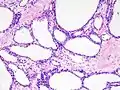

| Micrograph showing a pancreatic serous cystadenoma. H&E stain. | |

Pancreatic serous cystadenoma is a benign tumour of the pancreas.[2] It is usually solitary and found in the body or tail of the pancreas, and may be associated with von Hippel–Lindau syndrome.[2]

Pathologists classify serous cystic neoplasms into two broad groups. Those that are benign, that have not spread to other organs, are designated "serous cystadenoma".[5] Serous cystadenomas can be further sub-typed into microcystic, oligocystic (or macrocystic), solid, mixed serous-endocrine neoplasm, and VHL-associated serous cystic neoplasm. This latter classification scheme is useful because it highlights the range of appearances and the clinical associations of these neoplasms. Serous cystic neoplasms that have spread ("metastasized") to another organ are considered malignant and are designated "serous cystadenocarcinoma".